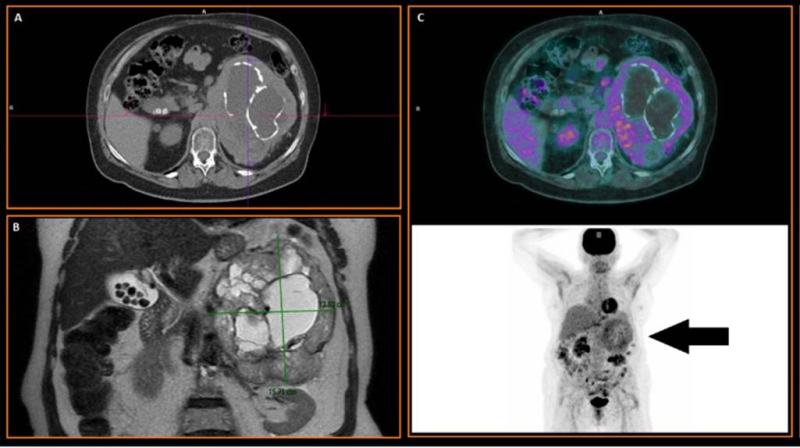

Mujer de 73 años con antecedentes de osteoporosis, portadora de hipertensión arterial (HTA) refractaria al tratamiento, en estudio por dolor abdominal, episodios de diarrea tipo secretora y pérdida de peso. A la exploración se destacaba sudoración profusa y masa palpable en hipocondrio izquierdo. En la tomografía axial computarizada (TAC) se descubre una tumoración adrenal izquierda de 15x3x16 cm, heterogénea y con calcificaciones, que desplaza estructuras adyacentes (fig.1A). En RMN presentó grandes áreas quísticas centrales (algunas hemorrágicas), componente sólido predominantemente periférico, restricción en difusión y bajos valores en mapa ADC, lo que sugería carcinoma suprarrenal o sarcoma retroperitoneal (fig.1B). Los niveles de catecolaminas/metanefrinas en orina se encontraron elevados.

El estudio híbrido PET/CT con 18F-FDG mostró una gigantesca masa suprarrenal izquierda con incremento metabólico en su periferia (SUVmáx = 5,5) y ausencia de captación en los componentes quísticos centrales y áreas calcificadas. Dichos hallazgos eran compatibles con proceso neoformativo, cuyo grado metabólico no sugería carcinoma (fig.1C). Finalmente, la gammagrafía simpáticoadrenal con 370 MBq de 123I-MIBG y técnica híbrida SPECT/CT reveló intenso depósito focal del trazador a nivel de la glándula suprarrenal izquierda, correspondiente a un feocromocitoma con necrosis intratumoral asociada (fig. 2). Se inició bloqueo-alfa preoperatorio (fenoxibenzamina 5 mg) y se realizó suprarrenalectomía izquierda con nefrectomía ipsilateral en segundo tiempo. El estudio anatomopatológico confirmó feocromocitoma maligno con PASS-score (Pheochromocytoma of Adrenal gland Scaled-Score) de 7, potencial alto de malignidad. Actualmente la paciente se encuentra asintomática, habiendo cedido los episodios diarreicos y con normalización de cifras tensionales tras la cirugía.